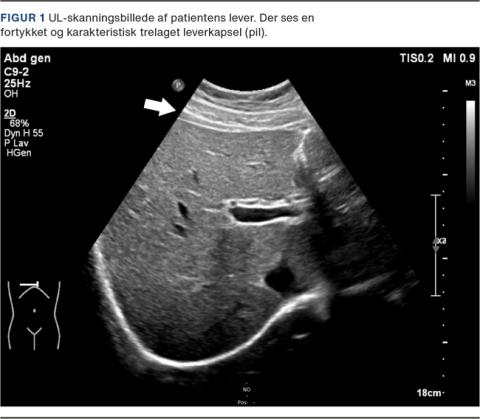

Klamydiapodningen var positiv, og derfor opstod der mistanke om FHCS. Ved en sekundær gennemgang af UL-skanningen af leveren sås en fortykket og tredelt kapsel (Figur 1). CA-125-niveauet var 140 kE/l, hvilket man antog var reaktivt forhøjet.

Diagnosen er primært klinisk og støttes ved udelukkelse af differentialdiagnoser, f.eks. galdesten, og identifikation af patogenet [2].Kardinalsymptomet er smerter under højre kurvatur, og smerterne forværres ved bevægelse og vejrtrækning. Der kan desuden være febrilia og tegn på PID [1].Paraklinisk findes der forhøjet CRP-niveau, typisk under 90 nmol/l, hvorfor det høje CRP-niveau hos patienten i sygehistorien er usædvanligt. Lever-galde-værdier er ved FHCS typisk upåvirkede [2].Ved UL-skanning af leveren kan der ses en fortykket og trelaget leverkapsel [3]. Ved CT med kontrast kan der ses en fortykket og opladende leverkapsel i arteriefasen [1].